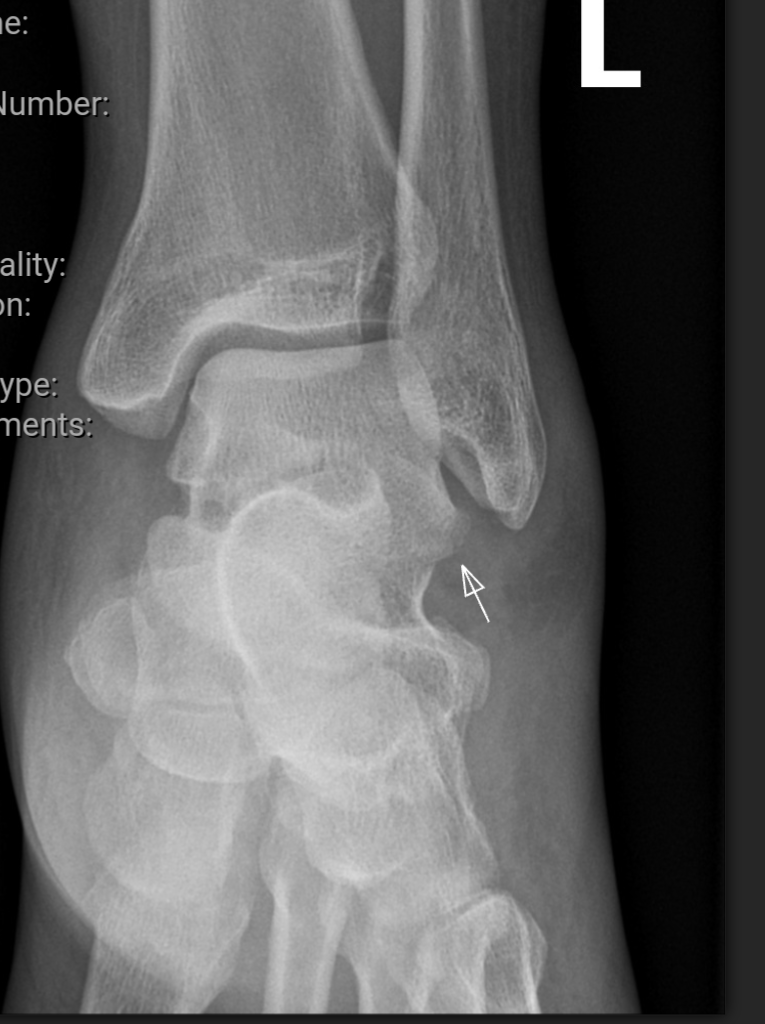

발등 위 부분에 실금이 간 Talus fractures 라고 한다.

골절이 없었다면 2주가 지난 지금은 살짝 움직일 정도가 되야 하는데 붓기도 안 빠지고 발을 땋게 딛을 수도 없는 이유가 그 때문이라고..